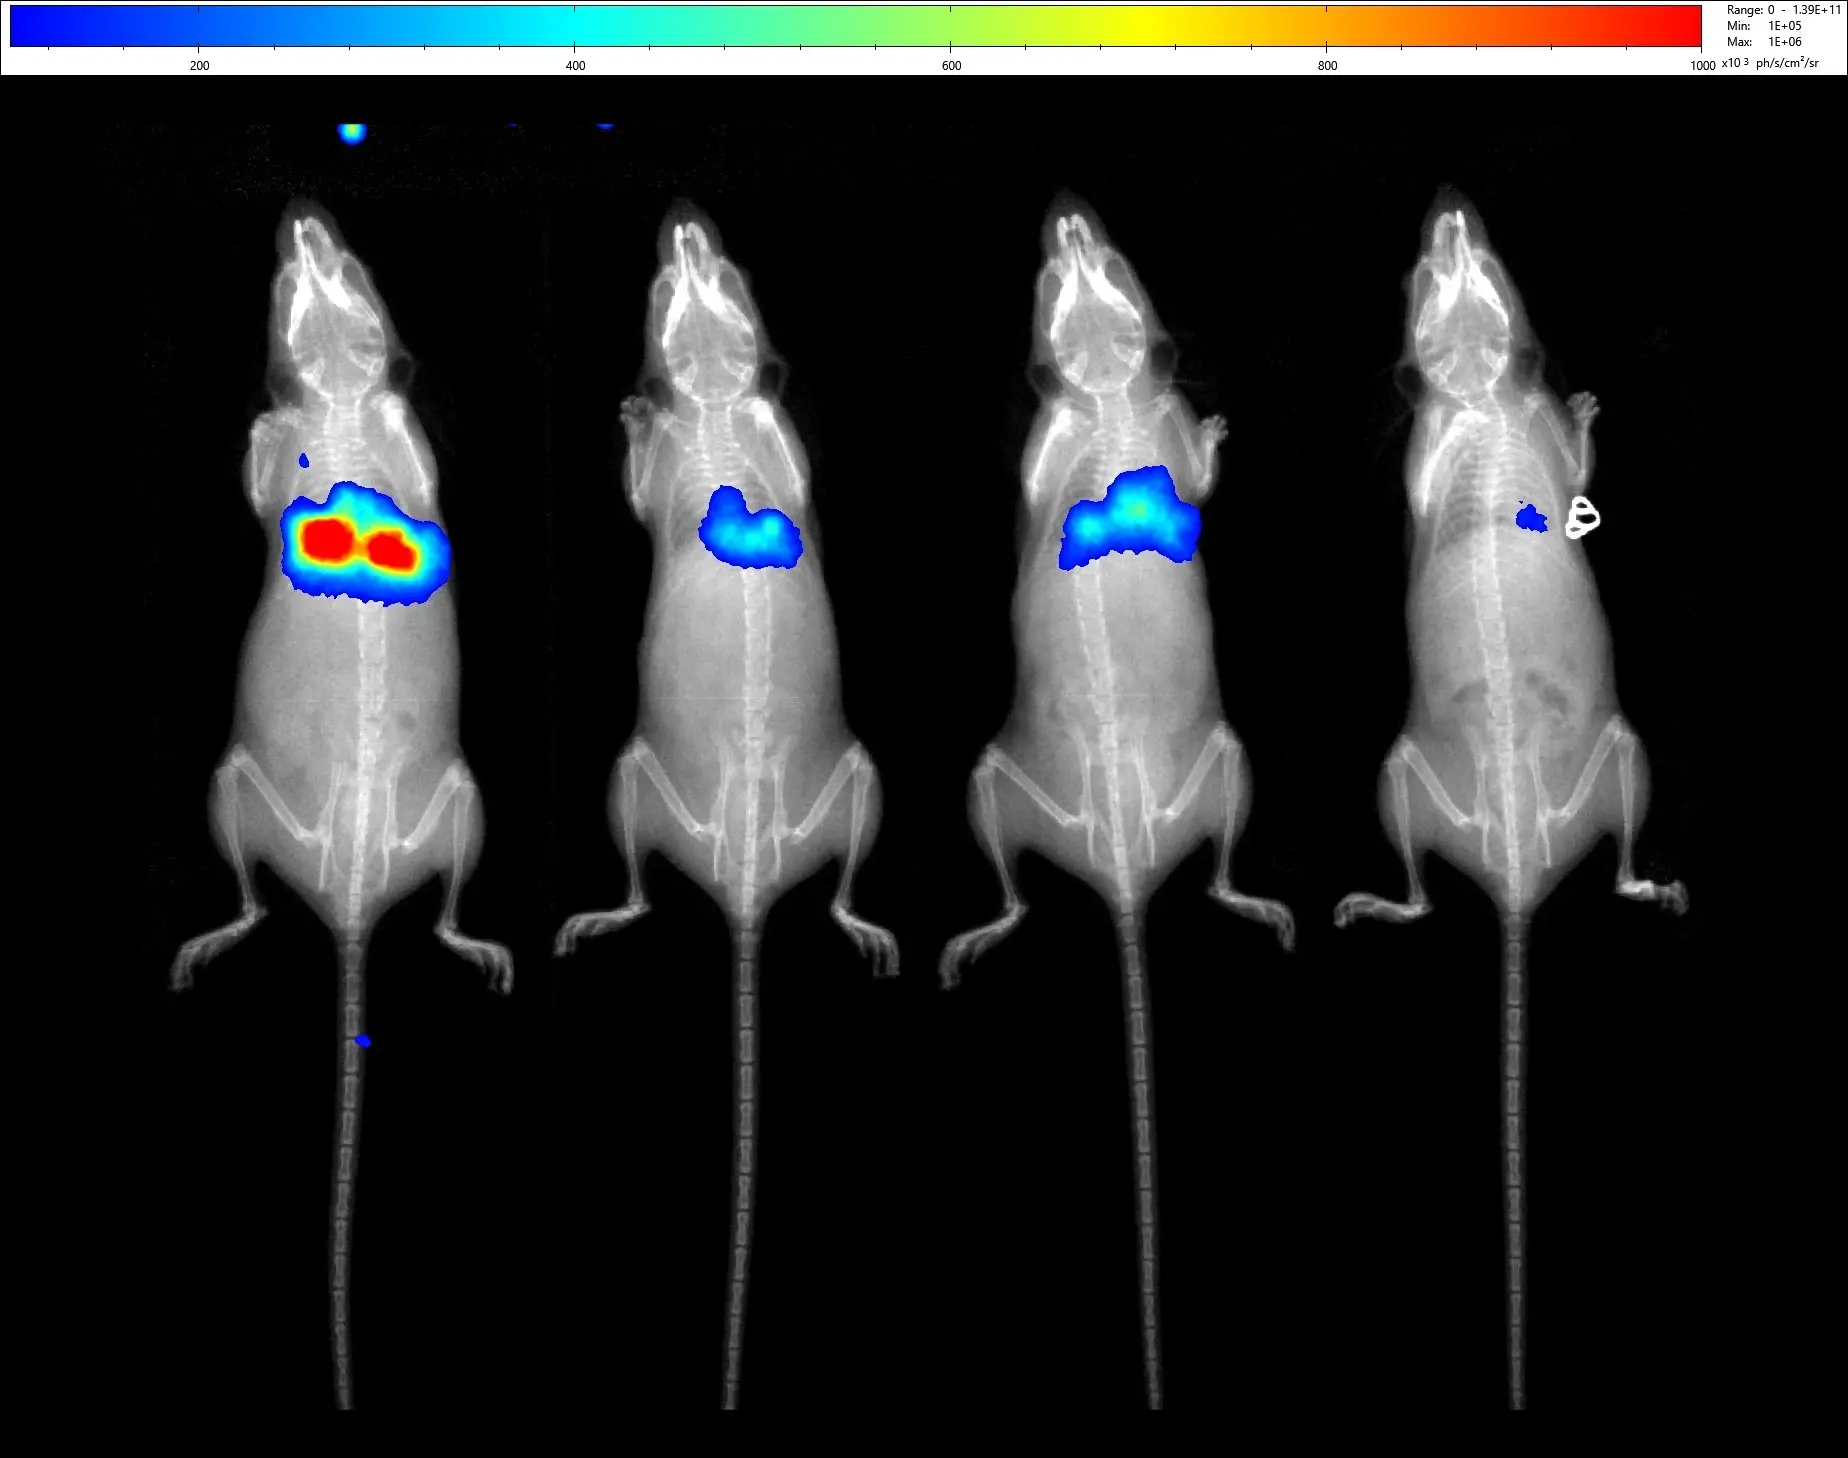

The In Vivo Department focuses its activities on multimodal preclinical imaging, including isotopic techniques (PET, SPECT, and autoradiography), X-ray imaging (µCT), magnetic resonance imaging (MRI 9.4T and 1T), optical imaging (BLI, FLI, and CLI), and photoacoustic imaging (MSOT).

Its research activities cover a broad range of application fields, including oncology, inflammation, drugs biodistribution, skeletal disorders, cell tracking (stem cells, parasites, …), and infectiology, angiology (angiography, hypoxia, …).

iThera Medical, inVision Echo for simultaneous optoacoustic and ultrasound tomography, equipped with internal mouse and small rat holders, and 3D Cup hand-held detector. - Optical Imaging

Biospace Lab, PhotonImager Optima for simultaneous imaging of up to 10 mice and imaging of other small animals such as rats, eels, zebrafishes, … Multimodal system designed for bioluminescence, fluorescence and Cherenkov luminescence imaging, and also equipped with additional 4-Views, MACROLENS and X-Rays modules. - Near-infrared fluorescence imaging